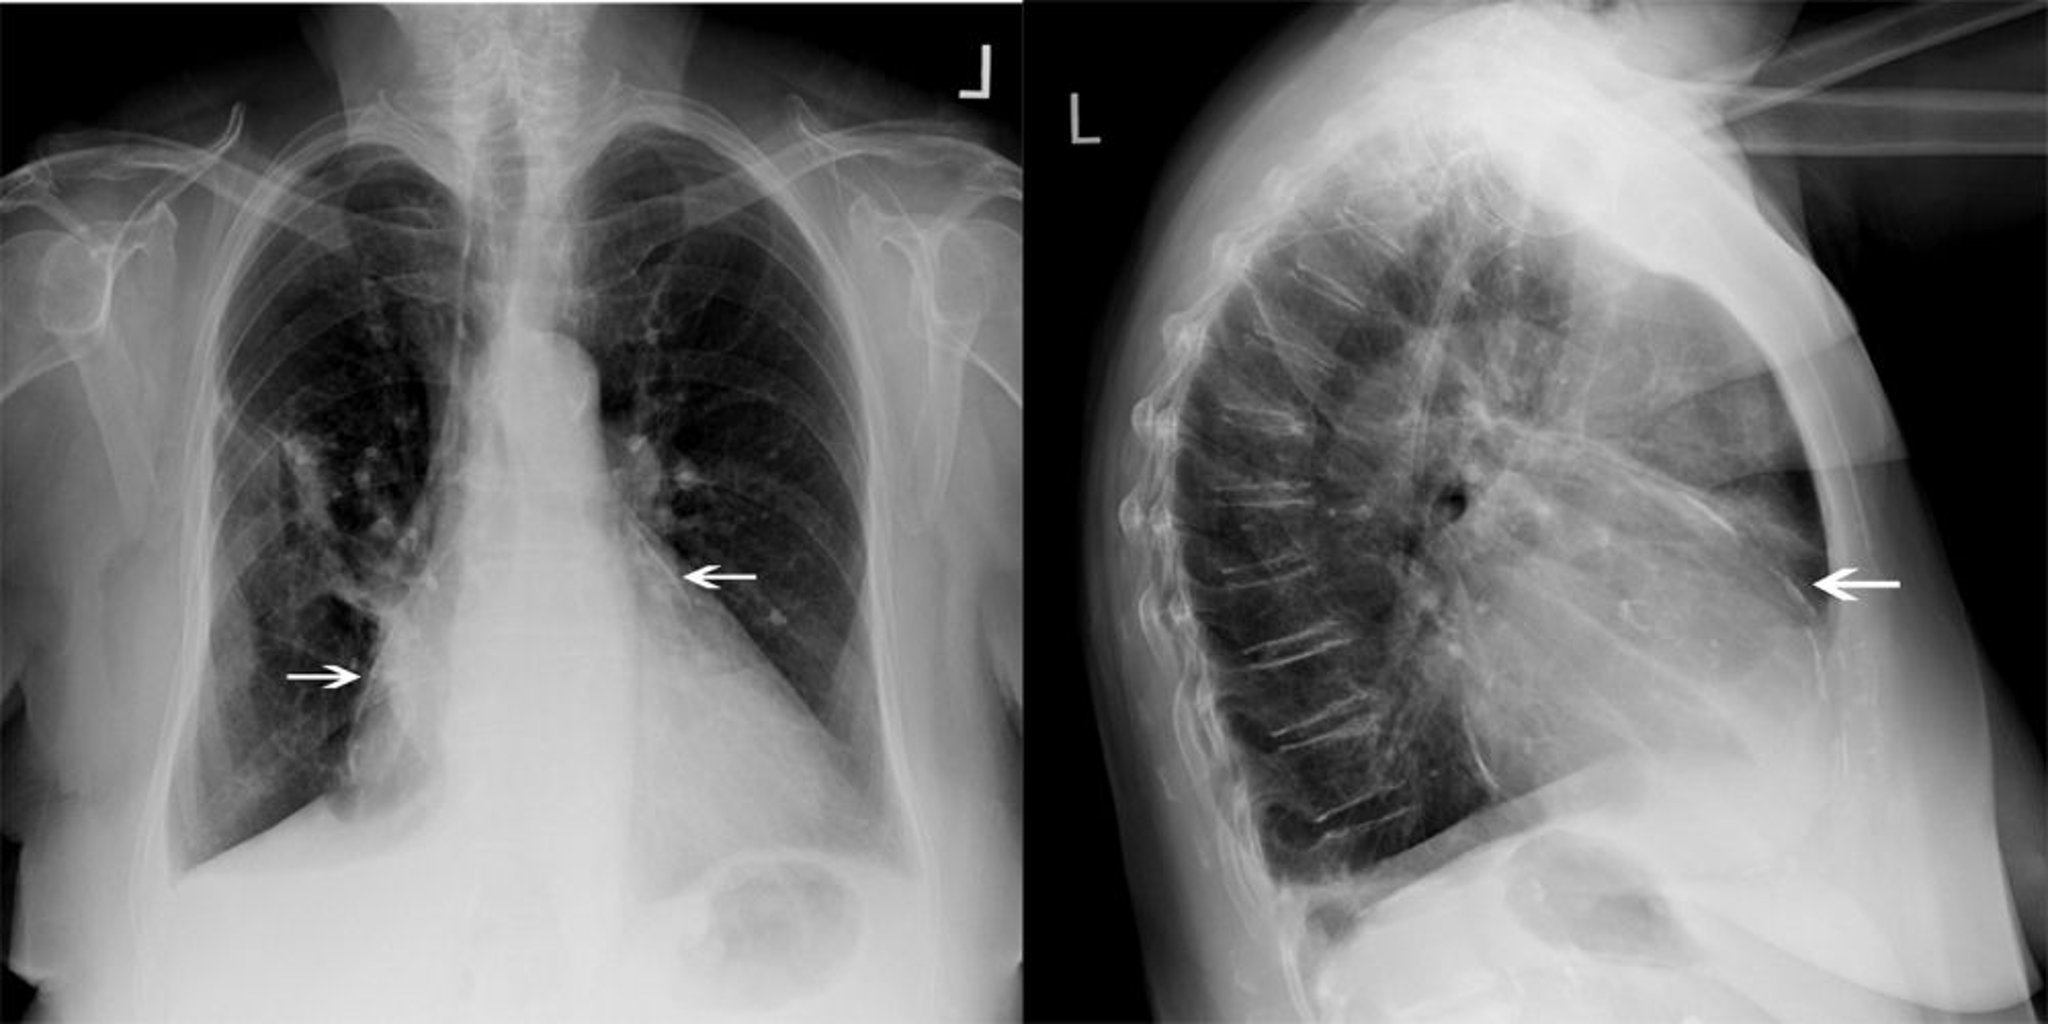

Diagnosis is suggested by clinical findings but often is suspected only after finding an enlarged cardiac silhouette on chest radiograph. On ECG, QRS voltage is often decreased, and sinus rhythm remains in most patients. With large, chronic effusions, the ECG may show electrical alternans (ie, P, QRS, or T wave amplitude increases and decreases on alternate beats). Electrical alternans is associated with variation in cardiac position (swinging heart).

Although CT can detect a pericardial effusion (often incidentally on a scan done for other conditions), it may overestimate its size and is not a first-line test to evaluate possible pericardial effusion.

Lateral chest x-ray often shows pericardial calcification best, but the finding is nonspecific.